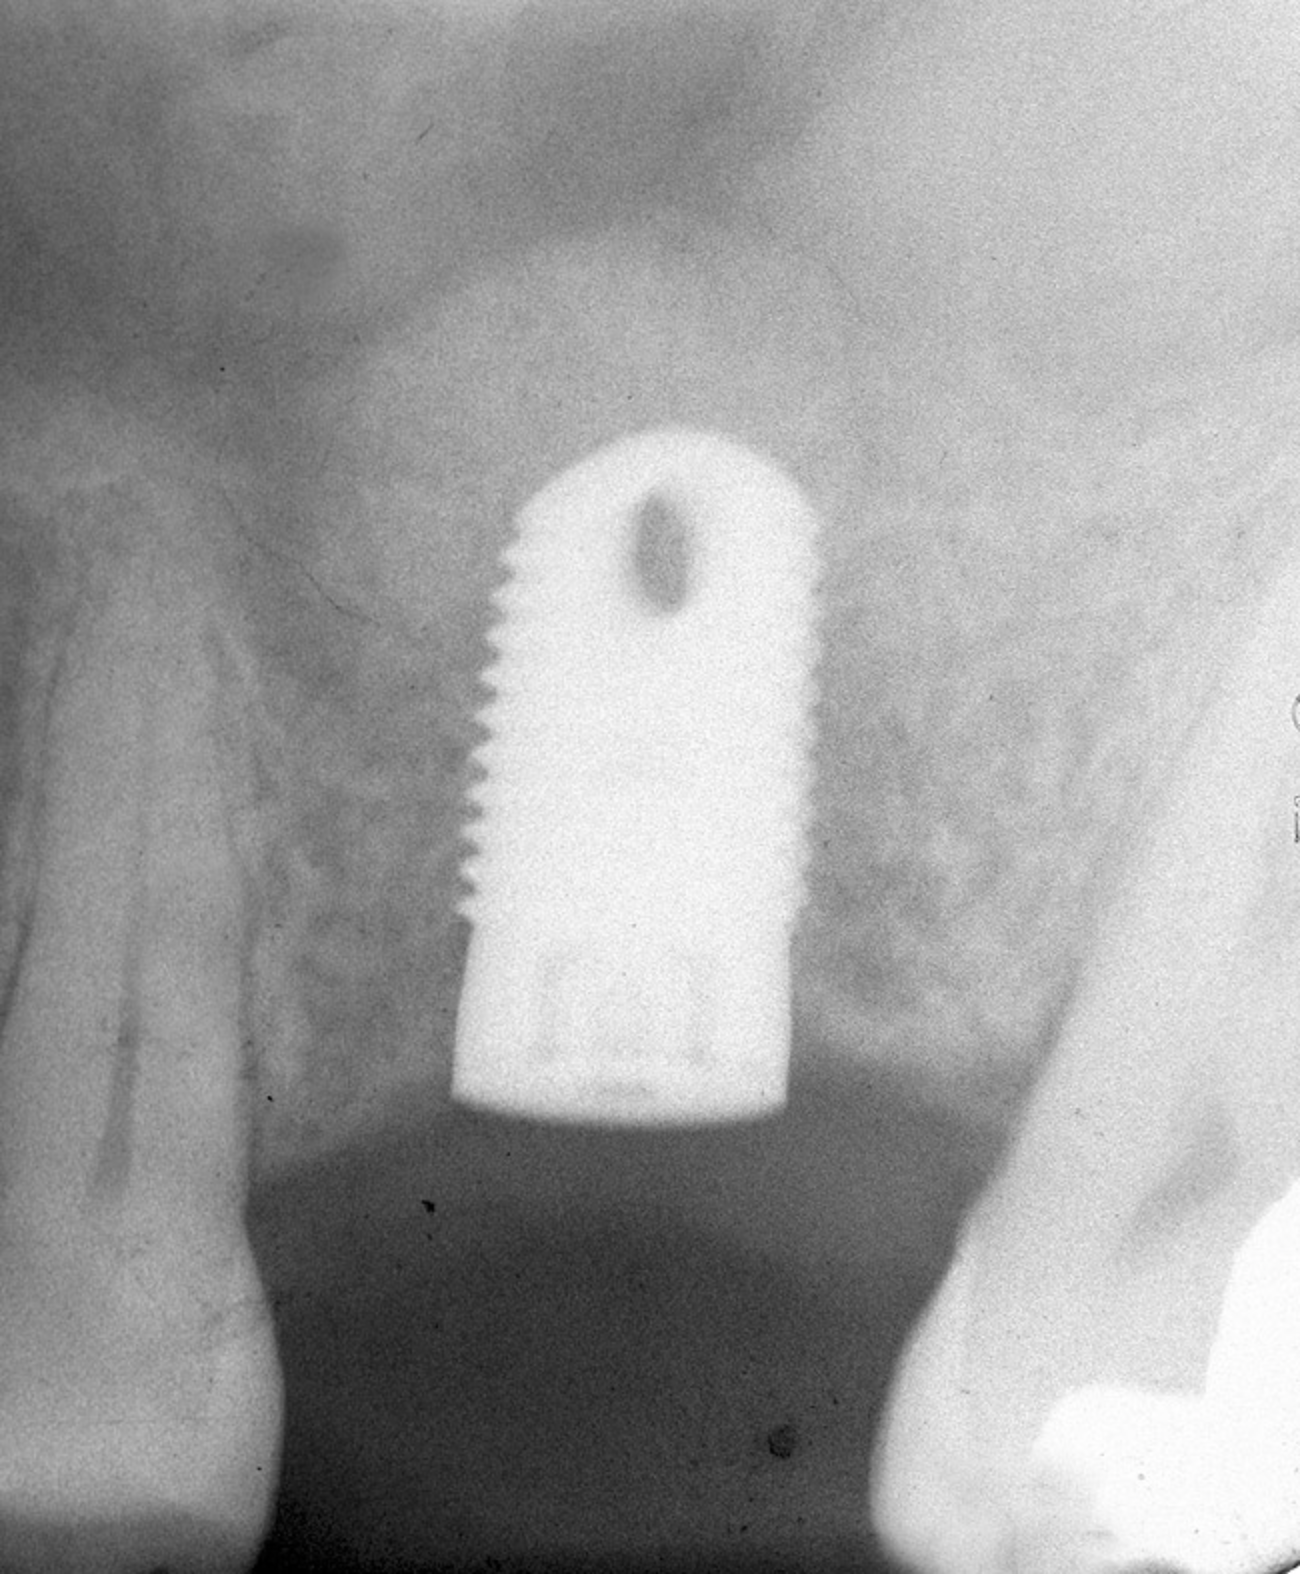

First, a periapical radiograph is taken to determine the amount of bone subantrally. It should be noted that a periapical film has an average error of 14%.23 Therefore, it is advantageous to take the radiograph in a manner that includes a marker (5-mm wide ball bearing) in order to be able to calculate the magnitude of radiographic error (Figure 1).

Figure 1  At tooth site No. 14, a periapical radiograph was taken with the long-cone paralleling technique. The radiographic ball marker measured 5.8 mm while its actual diameter is 5 mm. The enlargement is 0.8 mm, therefore the magnification error is 0.8/5 = 16%. By correcting for this error, a closer approximation of the amount of bone from the osseous crest to the sinus floor can be made.

Figure 1